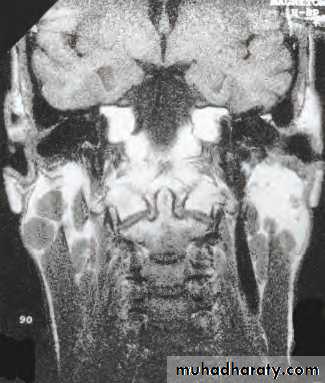

Rarely arise from deep lobe and present as paraphryngeal mass.

Symptoms include difficulty in swallowing and snoring. Clinically there is diffuse firm swelling in the soft palate and tonsils